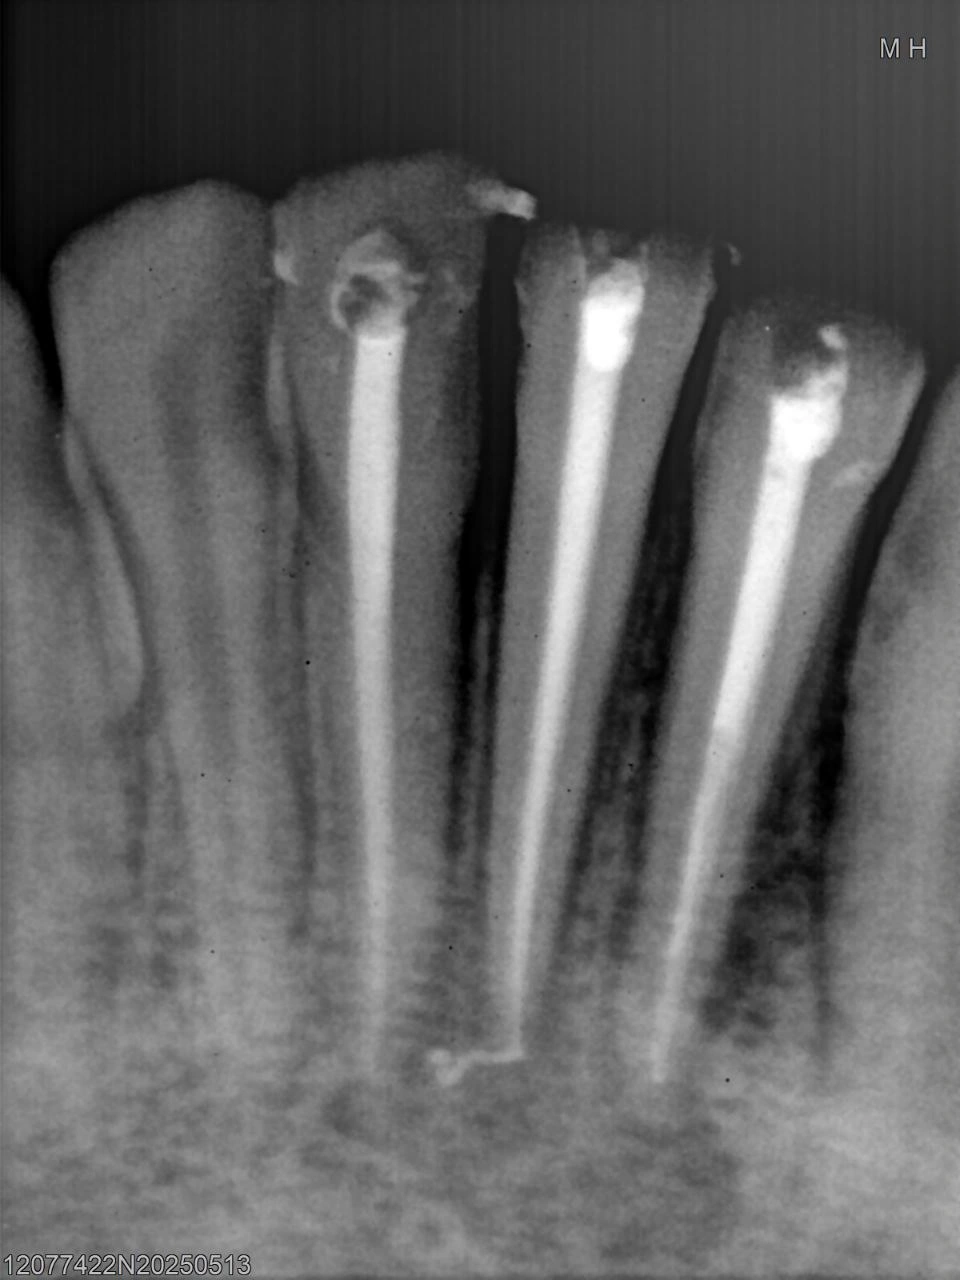

Post-operative radiograph showing complete obturation and apical seal.